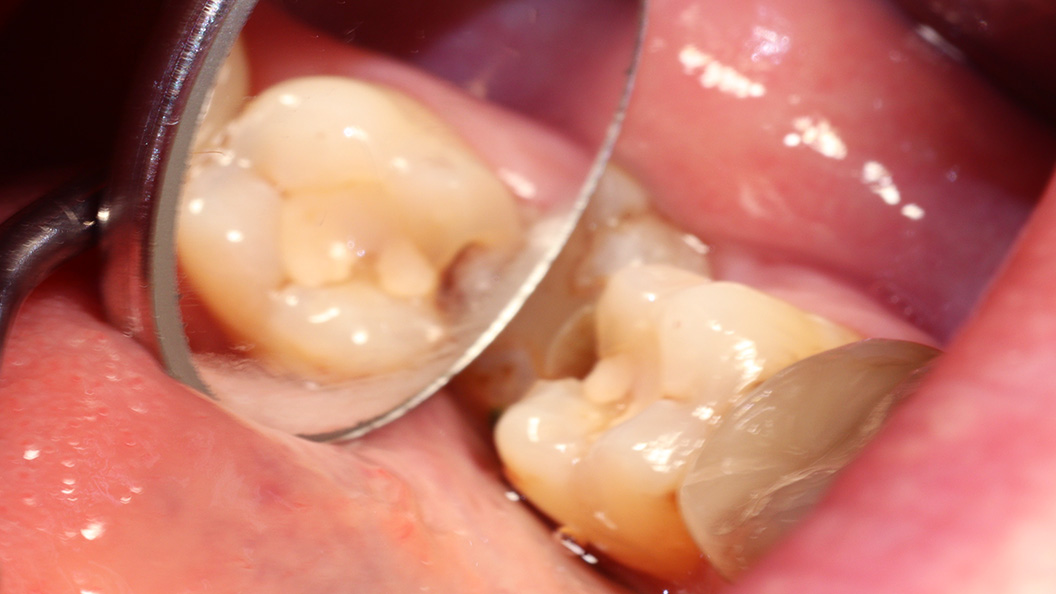

В нашу клинику обратилась пациентка с жалобами на выпадение пломбы из 37 зуба. Её беспокоили кратковременные болевые ощущения от холодного и при попадании пищи. Во время осмотра был поставлен диагноз: хронический глубокий кариес 37 зуба (медиально-окклюзионно-дистально).

В случае возникновения болевых ощущений при приёме пищи, реакции на холод или сладкое я рекомендую обязательно обращаться к врачу. Если оставить ситуацию без внимания, то воспалительный процесс будет прогрессировать и распространяться глубже, в пульпу. Это чревато пульпитом, а значит потребуется намного более сложное и длительное лечение.